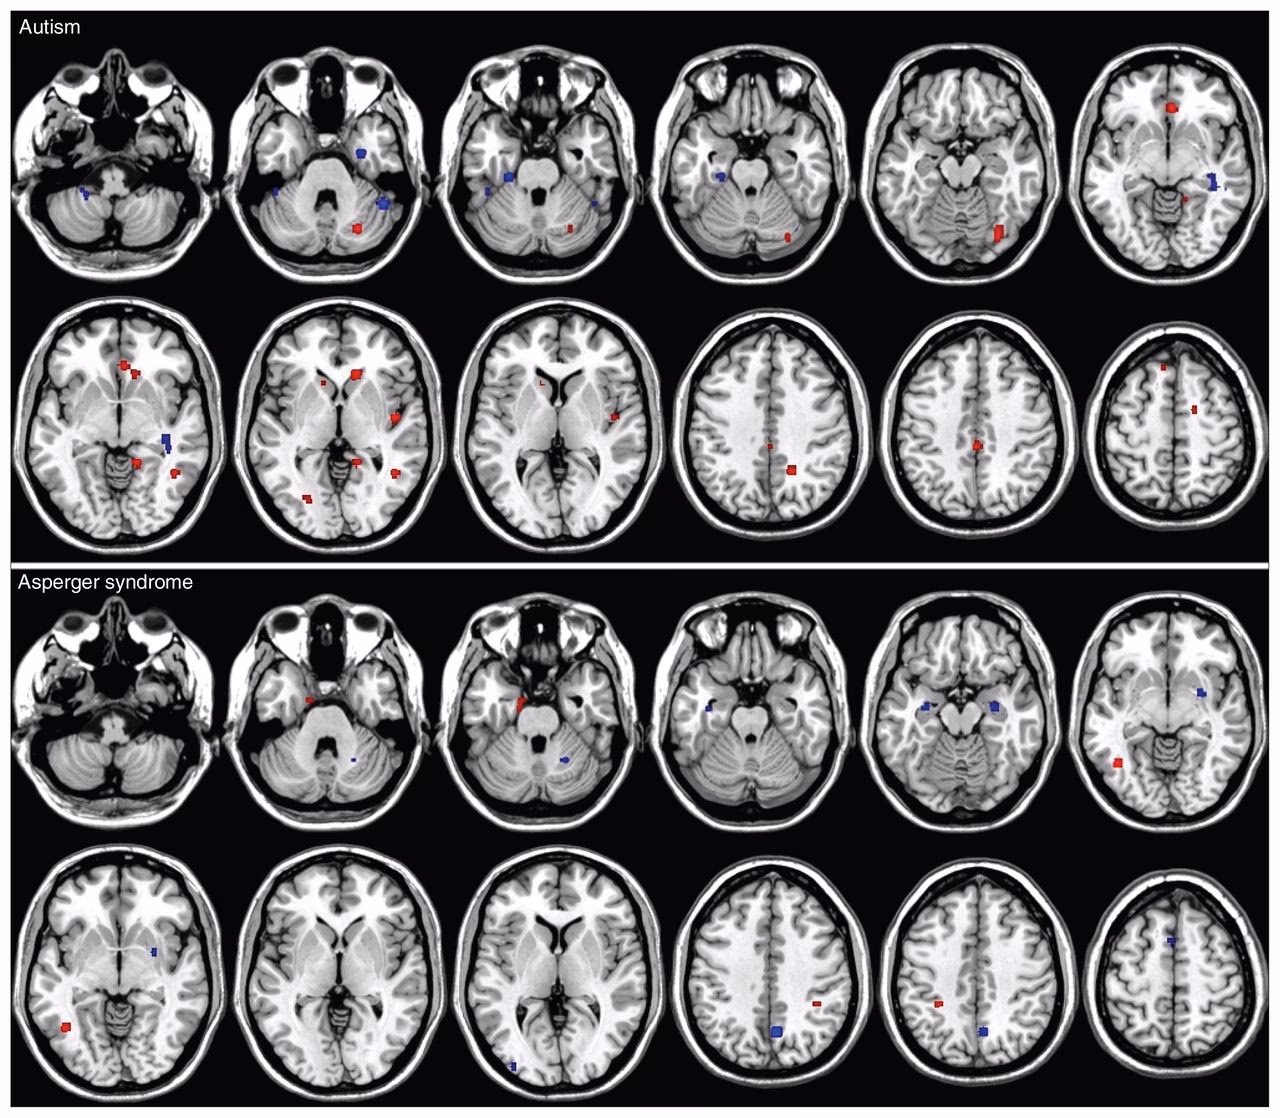

Las investigaciones sobre la anatomía cerebral en el Síndrome de Asperger, aunque aún en desarrollo, han comenzado a arrojar luz sobre las posibles bases neurobiológicas. A diferencia de la búsqueda inicial de una única lesión cerebral específica, los estudios más recientes, a menudo utilizando técnicas de resonancia magnética cuantitativa, sugieren diferencias generalizadas en el desarrollo cerebral que, sin embargo, se asocian con particularidades notables en regiones específicas.

Un estudio comparativo entre adultos con Síndrome de Asperger y un grupo de control encontró varias diferencias significativas. Por un lado, se observaron patrones de cambio volumétrico relacionados con la edad distintos. Mientras que en el grupo de control se apreciaba una reducción volumétrica asociada a la edad en los hemisferios cerebrales y los núcleos caudados, estas reducciones no eran evidentes en el grupo con Asperger. Esto podría sugerir trayectorias de desarrollo o envejecimiento cerebral diferentes.

Más allá de los cambios relacionados con la edad, las personas con Asperger mostraron consistentemente menos materia gris en regiones fronto-estriatales y cerebelosas en comparación con el grupo de control. Las regiones fronto-estriatales, que incluyen partes de la corteza prefrontal y los ganglios basales (como el núcleo caudado), son cruciales para funciones ejecutivas, planificación, control de impulsos y flexibilidad cognitiva. El cerebelo, tradicionalmente asociado con la coordinación motora, también desempeña roles importantes en la cognición, el lenguaje y las emociones.

Además de las diferencias en la materia gris, se encontraron diferencias generalizadas en la materia blanca. La materia blanca consiste en haces de fibras nerviosas (axones) cubiertas de mielina que conectan diferentes regiones del cerebro. Las diferencias en la materia blanca pueden indicar patrones de conectividad alterados, lo que podría afectar la eficiencia y la sincronización de la comunicación entre distintas áreas cerebrales.